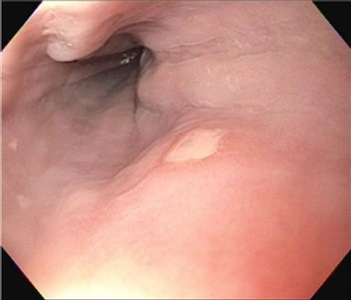

A 45-year-old female presented to our emergency department with severe, acute onset headaches. Her workup revealed lytic lesions in the calvarium and diffuse FDG avid lymphadenopathy (figure 1). Subsequent workup including biopsies of right inguinal, mediastinal and right axillary lymph nodes, and bone marrow, failed to demonstrate any etiology.

Figure 1: